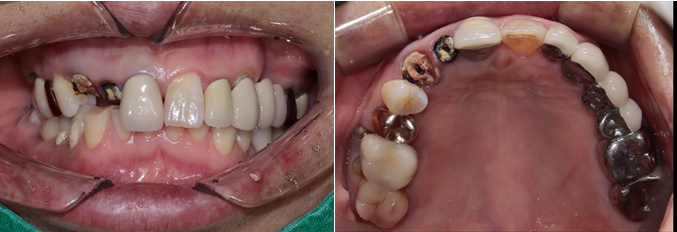

전치부는 지르코니아, 구치부는 보험임플란트 pfm 으로 제작 (70세 여자)

c.c: 앞니가 부러졌고, 오른쪽 어금니가 아파요.